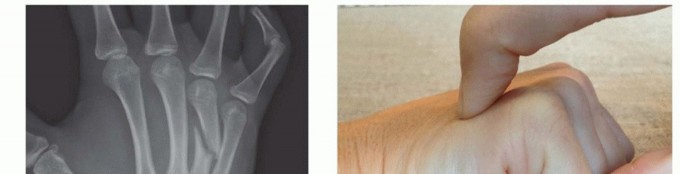

A rigorous, systematic clinical assessment is the first step in preoperative planning. Inspection must evaluate the hand at rest, noting the natural digital cascade, and through a full active arc of motion. The surgeon must critically assess for any deviation of the nail beds during flexion, the hallmark of rotational malalignment. Palpation should trace the dorsal contour of the metacarpals to identify fracture step-offs, while simultaneous volar palpation assesses for symptomatic metacarpal head prominence. The surgeon must maintain a high index of suspicion for associated injuries, meticulously examining the skin for subtle puncture wounds over the MCP joints that signify a human tooth strike, and evaluating the CMC joints for subtle subluxations that frequently accompany basilar fractures.

For transverse or short oblique fractures of the metacarpal neck and shaft, particularly in the fifth metacarpal, percutaneous or minimally invasive intramedullary techniques offer excellent stability while sparing the dorsal soft-tissue envelope. The procedure begins with a closed reduction utilizing the Jahss maneuver: the MCP and PIP joints are flexed to 90 degrees, relaxing the intrinsic muscles and tightening the collateral ligaments, allowing the proximal phalanx to be used as a lever to push the metacarpal head dorsally, correcting the apex-dorsal angulation.

Clinical & Radiographic Imaging Archive